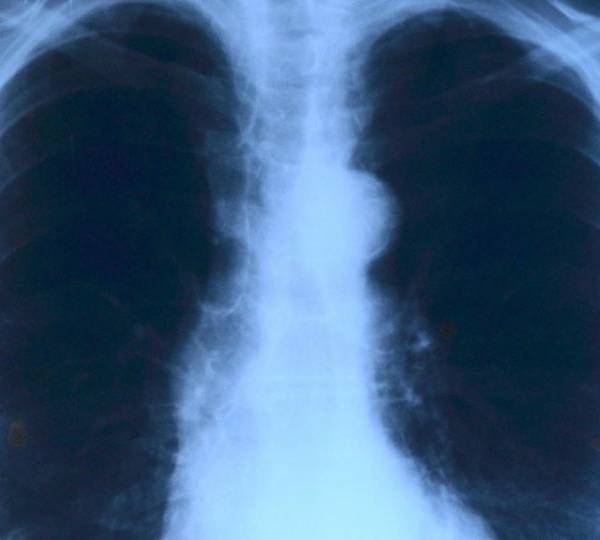

Quienes sufren de fibrosis quística padecen de una mucosidad que afecta sus pulmones y otras partes del cuerpo. Foto: Pixabay